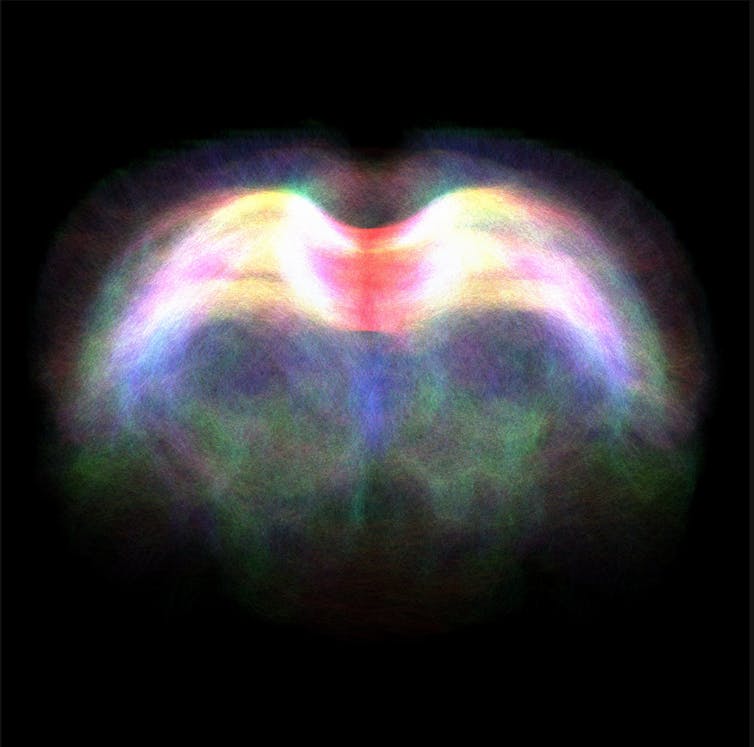

This image shows diffusion tensor imaging, an MRI-based neuroimaging technique, revealling the fibre tracts through the corpus callosum in a rodent brain. The corpus callosum links the brain’s left and right hemispheres to each other. The colours represent the different directions that the tracts are travelling through the brain.